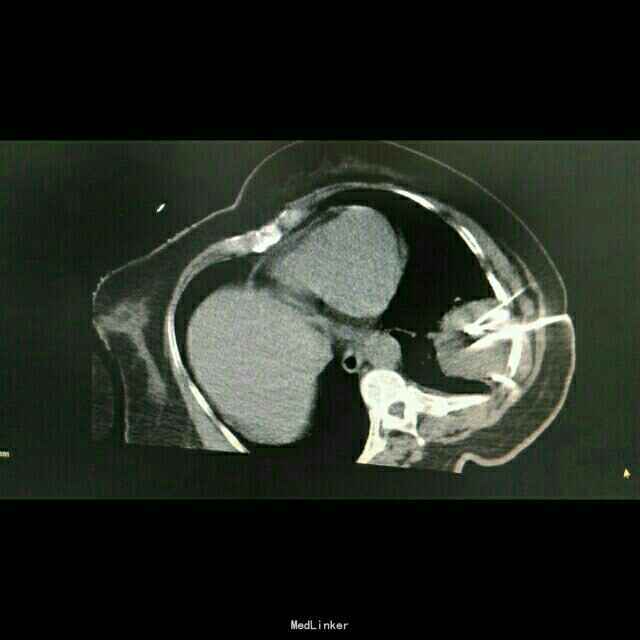

查体:体温:36℃,脉搏:86次/分,呼吸:21次/分,血压:137/81mmHg,胸廓无畸形,两侧对称,双肺呼吸动度一致,左下肺呼吸音减弱,未闻及干湿罗音。心率:86次/分,律齐,心前区及各瓣膜听诊区未闻及杂音,腹软,无压痛及反跳痛。双下肢体无水肿。 辅助检查:胸部CT示:左肺下叶,双肺多发转移灶。于10月16日行左侧胸腔积液穿刺引流,胸水病理检查示:可见少许核异型细胞,考虑为腺癌细胞 颅脑MR检查示:右侧小脑半球两处异常信号,转移瘤可能,右侧放射冠区陈旧性腔梗。

中医诊断: 肺积 正虚瘀结 西医诊断: 1.左肺占位性病变:双肺转移? 2.2型糖尿病 3.冠状动脉粥样硬化性心脏病 治疗经过:,于10月8日下午行左肺占位穿刺活检,病理回报示:不除外细支气管肺泡癌。于10月12日下午行左肺癌碘125粒源植入术,围手术期给予抗感染、支持治疗。于10月16日行左侧胸腔积液穿刺引流,胸水病理检查示:可见少许核异型细胞,考虑为腺癌细胞,给予胸腔药物灌注治疗。于10月25日-29日给予患者生物细胞免疫DC+CIK治疗。 患者家属拒绝静脉化疗,给予口服特罗凯治疗!

患者治疗后一月余行肺ct检查病灶肺部病灶明显缩小!口服特罗凯治疗耙向治疗!